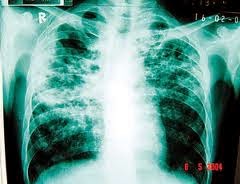

| Kuman TB menyerang paru-paru |

dahulu penyakit tibi yang juga dikenali sebagai batuk kering atau penyakit tuberkulosis begitu ditakuti. Ia adalah

disebabkan jangkitan bakteria Mycobacterium tuberculosis, yang menyerang

paru-paru.